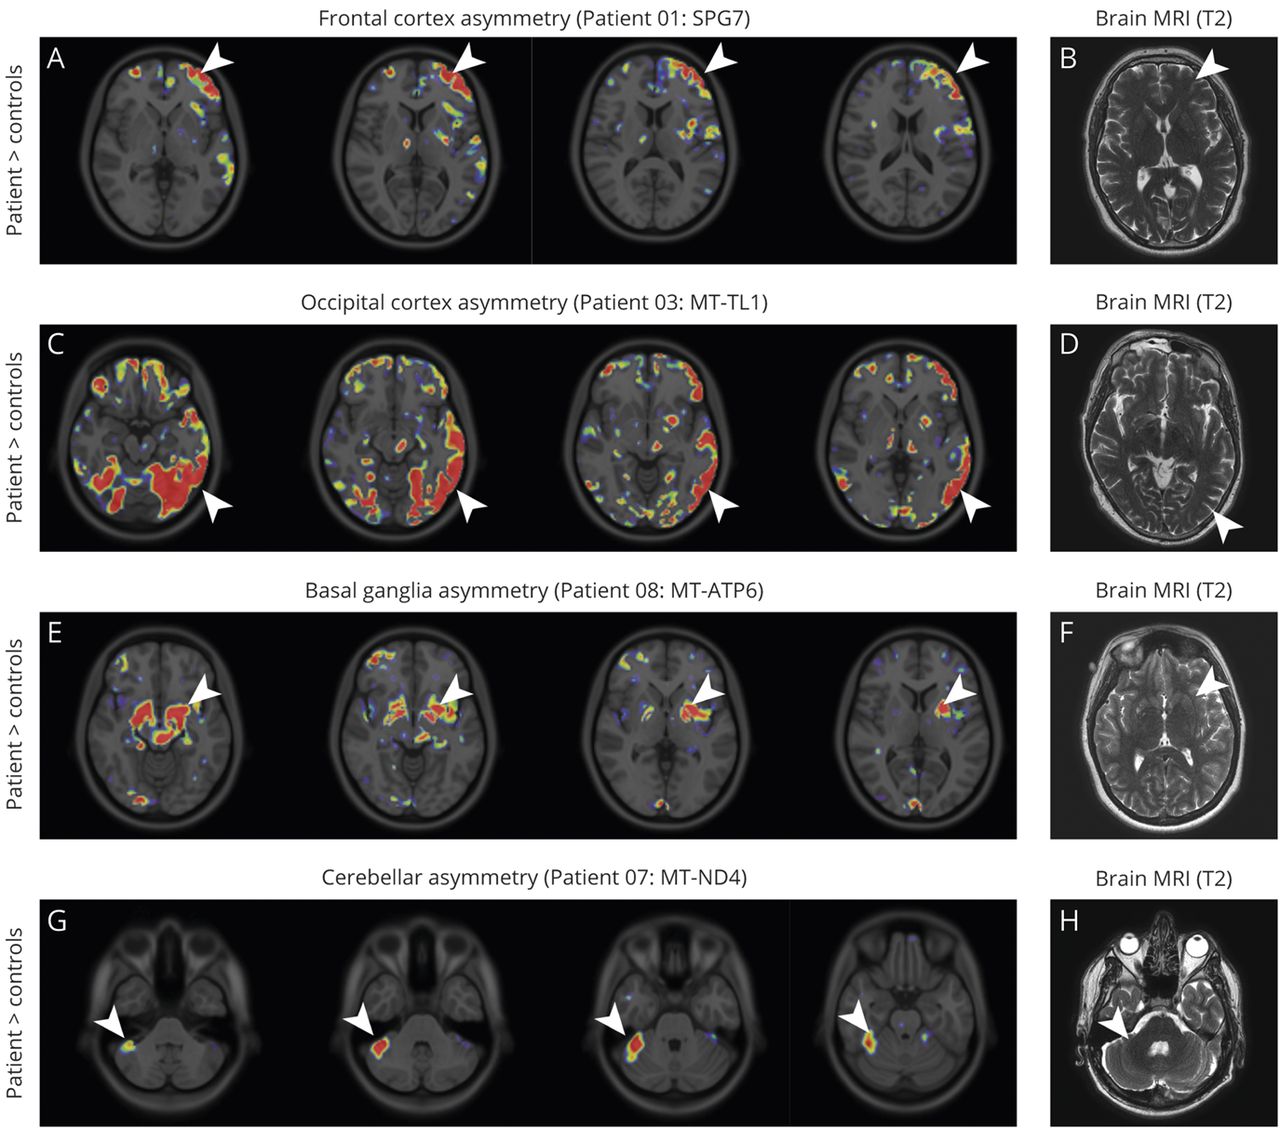

不对称的11C] P188金宝慱官网下载K11195绑定

许多(11C] P188金宝慱官网下载K11195宠物画面显示不对称信号改变大脑的特定区域(图5),没有明显的对应相应的MRI异常。最明显的例子不对称的放射性示踪剂绑定在大脑皮层(额叶皮层在病人1SPG7突变;枕叶皮质区和一个病人3MT-TL1突变;图5 A和C),基底神经节(病人8,MT-ATP6突变;图5 e7)或小脑(患者MT-ND4突变;图5克)。不对称信号变化不明确相关临床表现,在图中以增加信号的对侧小脑半球LHON患者(患者7;图5克)否则无症状(表)。